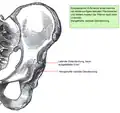

Die dysplastische Pfanne

Eine Hüftdysplasie führt zum Minderwachstum des Gelenks und somit zu einer minderwertigen Ausbildung der knöchernen Überdachung des Hüftkopfes. Der laterale und ventrale Pfannenerker sind nur teilweise oder gar nicht angelegt, was zu einer Dezentrierung des Hüftkopfes führt. Biomechanisch führen die unzureichende Überdachung und die Dezentrierung des Kopfes zu einer Verschiebung der Belastungszonen. Je kleiner die tragende Fläche (hier die dysplastische Pfanne), desto höher der entstehende Belastungsdruck (übertragen durch den Hüftkopf).[5]